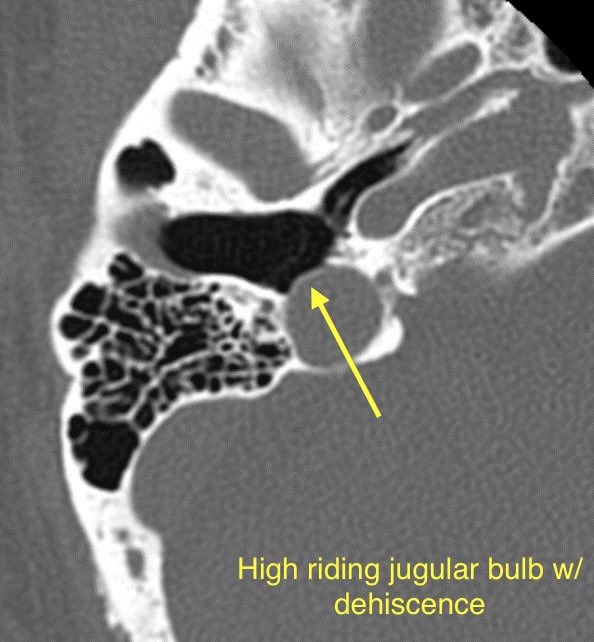

🔷JUGULAR BULB ABNORMALITIES

1️⃣High-riding jugular bulb

2️⃣Jugular bulb dehiscence

🔹High-riding jugular bulb is associated with jugular bulb dehiscence

💡"High" = within 2mm of the floor of the IAC, above the lower border of the round window, above the posterior semicircular canal, or above the basal turn of the cochlea

🔹Jugular bulb dehiscence: Thinning or visible defect of the jugular plate